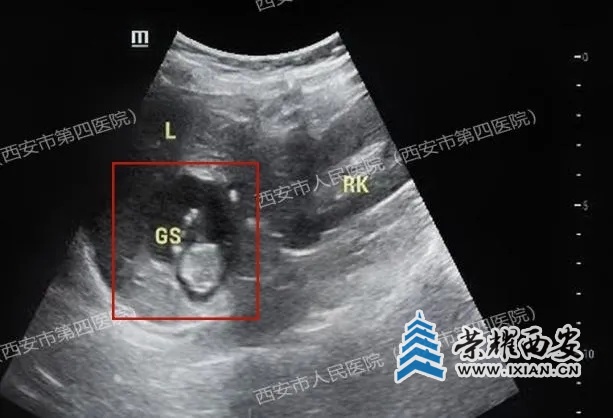

医生仔细扫查发现:

子宫内未见明显孕囊,右侧卵巢内小囊肿,双侧附件区未看见其他包块。通常,人绒毛膜促性腺激素(HCG)达到1000~2000mIU/ml左右就能看到孕囊,但王女士的HCG水平上升到9000mIU/ml时,超声却没有提示宫内孕囊。理论上来说即使真的宫外孕,包块应该很大、很明显,一眼就能找到才对啊?

Wq1aDm7QD8Ur9pBi.jpg

(上图腔内超声显示宫腔内未见孕囊,下图显示右侧卵巢小囊肿)